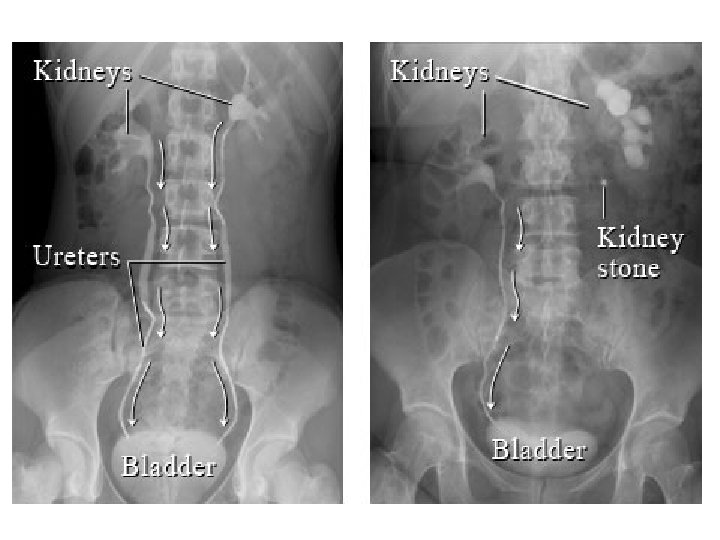

• DIAGNOZA DIFERENCIALE: - Appendisiti (ne fazen fillestare) - Pankreatiti - Patologjite renale dexter: infeksion apo kalkul ne ureter: *Anamneza *Ekzaminime laboratorik (urine) *Ekzaminime radiologjike te aparatit urinar

EKZAMINIMET LABORATORIKE: - Hemogram: Leukocitoze - Ekzaminimi i urines: per diagnoze diferenciale DIAGNOZA DIFERENCIALE: - Kolecistit - Kolika renale dexter - Ulcer gastroduodenale e perforuar - Okluzion intestinal

KOLIKAT RENALE